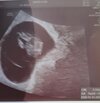

U mnie też tydzień młodsza. Ja jeszcze nie mam karty i skierowań, mam przyjść po świętach po to.Ja nie mam zdjęcia niestety, ale tez jest bijące serduszko. Z usg 5+5, wiec tydzień młodsza, ale mówiła, ze to jeszcze moze sie wyrównać.